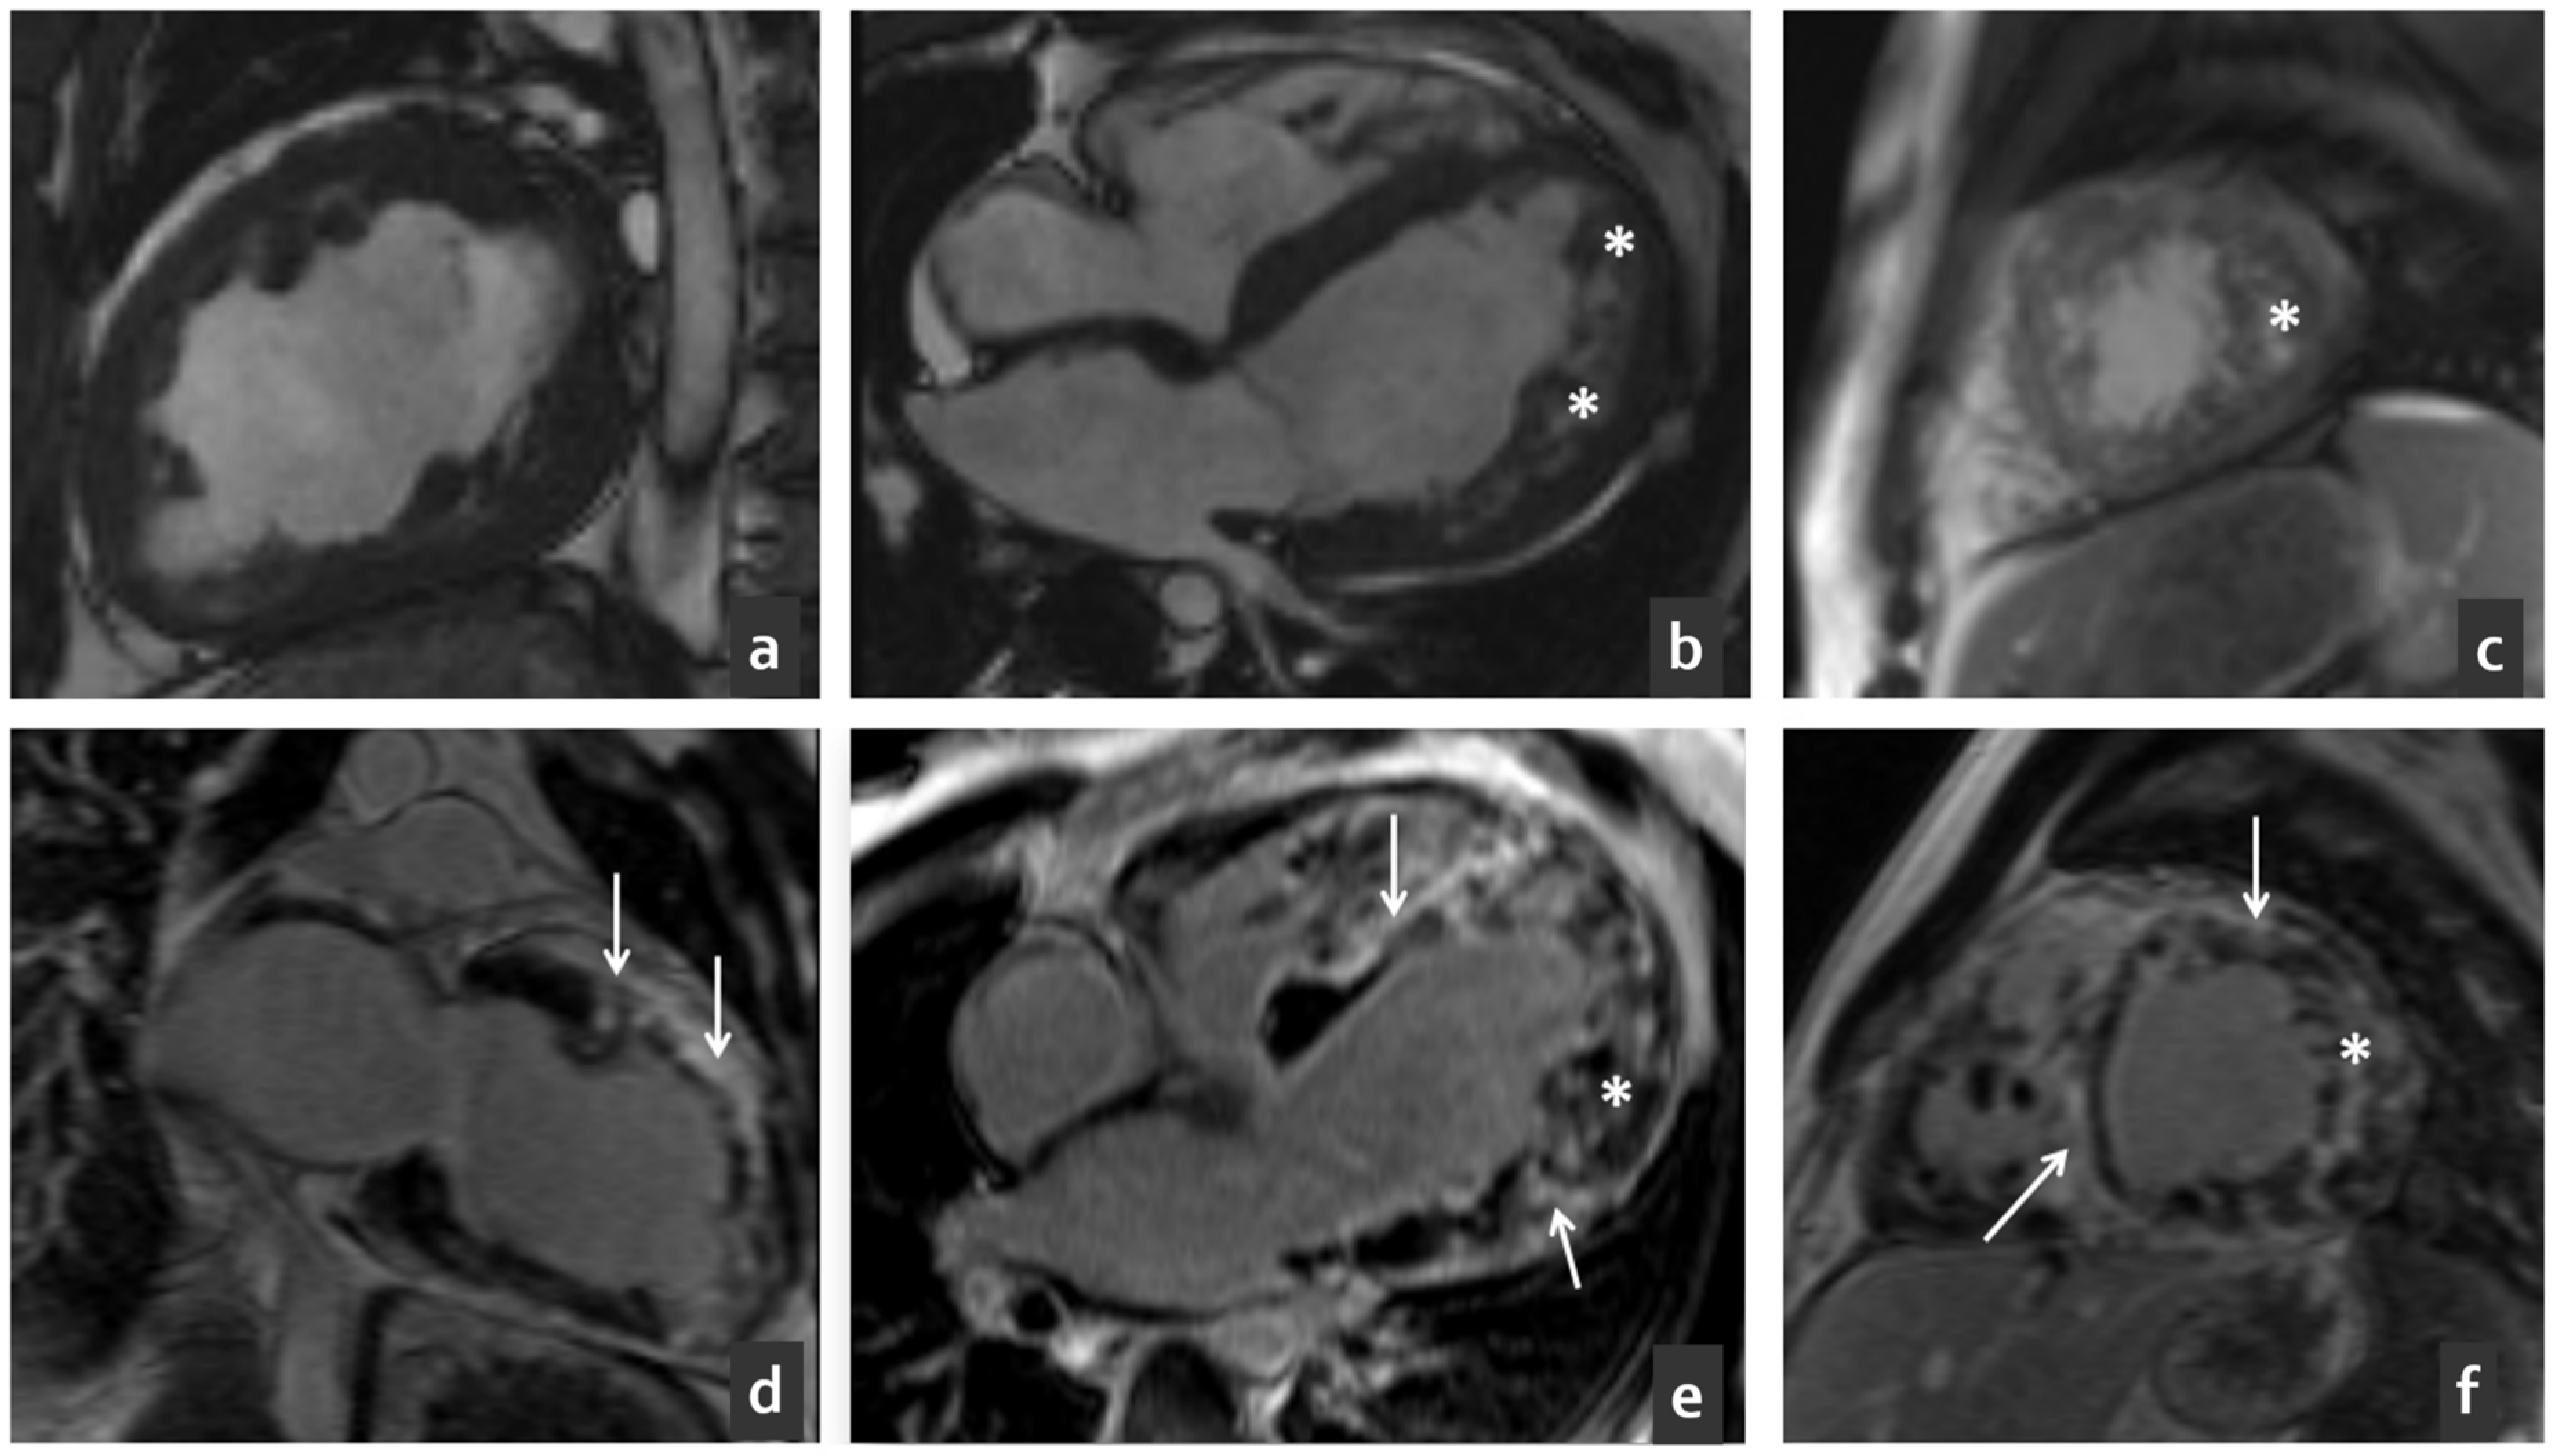

2.1. Clinical Characteristics of the Proband

2.2. Phenotypic Cascade Screening of the Relatives